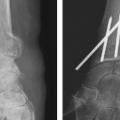

Le traitement chirurgical, justifié en cas de déplacement non tolérable, repose sur 3 modalités pratiques distinctes : l’embrochage percutané, les plaques palmaires vissées, et le fixateur externe radiométacarpien, à ne jamais utiliser seul. Ces traitements remplissent le double rôle de réduction et de stabilisation de la fracture jusqu’à consolidation.

La mise en place des broches percutanées sont habituellement introduites dans le foyer de fracture, en arrière du radius, puis inclinées vers le bas pour réduire la bascule dorsale de la glène radiale et sont finalement fichées dans la corticale antérieure, épaisse, pour stabiliser la réduction obtenue. Il s’agit d’un embrochage « intrafocal » (dans le foyer de fracture). Une ou deux broches styloïdiennes dans le plan frontal complètent le montage. La bascule antérieure du fragment distal, la présence de refends articulaires, et la comminution métaphyso-épiphysaire sont indispensables à évaluer avant de proposer ce type de traitement et constituent des contre-indications relatives (fig. 12).

La mise en place de plaques palmaires nécessite un abord chirurgical antérieur et reste techniquement délicat, en particulier pour positionner la plaque en hauteur et pour la longueur des vis dont l’excès peut endommager les tendons extenseurs. L’indication phare reste les fractures métaphysaires à déplacement antérieur ou les comminutions métaphysaires étendues (fig. 13).

Enfin, le fixateur externe ne doit pas être utilisé seul car une traction excessive est un facteur de risque d’algo­neurodystrophie. Il doit être ajouté comme moyen de protection d’une ostéosynthèse par broche ou plaque précaire. Son rôle est de neutraliser les contraintes en compression sur l’extrémité inférieure du radius en cours de consolidation (fig. 14).